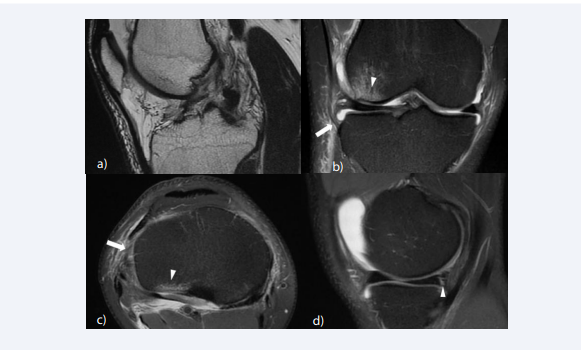

A Segond fracture is an avulsion fractures located at the lateral rim of the tibia, pathognomonic for an ACL tear [64,65] (Figure 4).

Segond fracture and Bosch-Bock bump. (A) Sagittal fat-suppressed T2-weighted image shows a complete tear of the ACL. (B) On coronal fat-suppressed T2- weighted image, a small avulsed bone fragment (white arrow) is noted at the lateral rim of the tibia (Segond fracture), which is a finding pathognomonic for an ACL  tear. (C) Corresponding CT images clearly depicts the Segond fracture. (D) The patient underwent ACL reconstruction surgery and on postoperative follow-up MRI  taken 2 years after the injury, the Segond fracture has healed, creating a characteristic bone excrescence at the lateral aspect of the proximal tibia (“Bosch-Bock bump”).

Figure 4 :Segond fracture and Bosch-Bock bump. (A) Sagittal fat-suppressed T2-weighted image shows a complete tear of the ACL. (B) On coronal fat-suppressed T2- weighted image, a small avulsed bone fragment (white arrow) is noted at the lateral rim of the tibia (Segond fracture), which is a finding pathognomonic for an ACL tear. (C) Corresponding CT images clearly depicts the Segond fracture. (D) The patient underwent ACL reconstruction surgery and on postoperative follow-up MRI taken 2 years after the injury, the Segond fracture has healed, creating a characteristic bone excrescence at the lateral aspect of the proximal tibia (“Bosch-Bock bump”).

Segond fractures occur from forced internal rotation and varus loading of the tibia relative to the femur [64,66]. They have been attributed to various structures; the mid-third lateral capsular ligament, the iliotibial band, the anterior arm of the biceps femoris tendon, the anterolateral ligament, and the anterolateral complex consisting of the ITB and anterolateral capsule [66-72]. Segond fracture has a reported prevalence of 2.4% to 29% in patients with ACL tears [64,65,73,74]. The healing of a Segond fracture may lead to a characteristic bone excrescence at the lateral aspect of the proximal tibia (“BoschBock bump”) [73] (Figure 4D).

Anterolateral ligament (ALL) injuries are found with varying severity and intensity in patients with acute ACL tear. ALL abnormalities have been reported to occur in 46 to 78.8% of ACL injuries in studies based on MR imaging [104,105] (Figure 9). The ALL functions as a stabilizer that resists anterior tibial translation, internal tibial rotation and pivot shifting, secondary to the ACL [106]. Failure to identify ALL injury may result in persistent instability following ACL reconstruction [107]. Concurrent reconstruction of the ACL and ALL significantly reduces internal rotation and axial plane tibial translation compared with isolated ACLR in the presence of ALL deficiency [108].

Associated injury of the anterolateral ligament (ALL) and medial meniscus (A) Oblique sagittal T2-weighted image shows a complete tear of the ACL at  the mid-substance. The proximal stump appears vertical to the Blumensaat line, whereas the distal stump appears horizontal. (B) On coronal fat-suppressed proton  density-weighted image, the ALL shows increased signal intensity near the tibial attachment (arrow) and periligamentous edema, indicating injury of the ligament.  Bone contusion is also noted at the lateral femoral condyle (arrowhead). (C) Axial fat-suppressed proton density-weighted image shows increased signal intensity of  the anterolateral ligament (arrow) and bone contusion at the posterior aspect of the lateral tibial plateau (arrowhead). (D) A vertical longitudinal tear is noted at the  posterior horn of the medial meniscus.

FIgure 9: Associated injury of the anterolateral ligament (ALL) and medial meniscus (A) Oblique sagittal T2-weighted image shows a complete tear of the ACL at the mid-substance. The proximal stump appears vertical to the Blumensaat line, whereas the distal stump appears horizontal. (B) On coronal fat-suppressed proton density-weighted image, the ALL shows increased signal intensity near the tibial attachment (arrow) and periligamentous edema, indicating injury of the ligament. Bone contusion is also noted at the lateral femoral condyle (arrowhead). (C) Axial fat-suppressed proton density-weighted image shows increased signal intensity of the anterolateral ligament (arrow) and bone contusion at the posterior aspect of the lateral tibial plateau (arrowhead). (D) A vertical longitudinal tear is noted at the posterior horn of the medial meniscus.